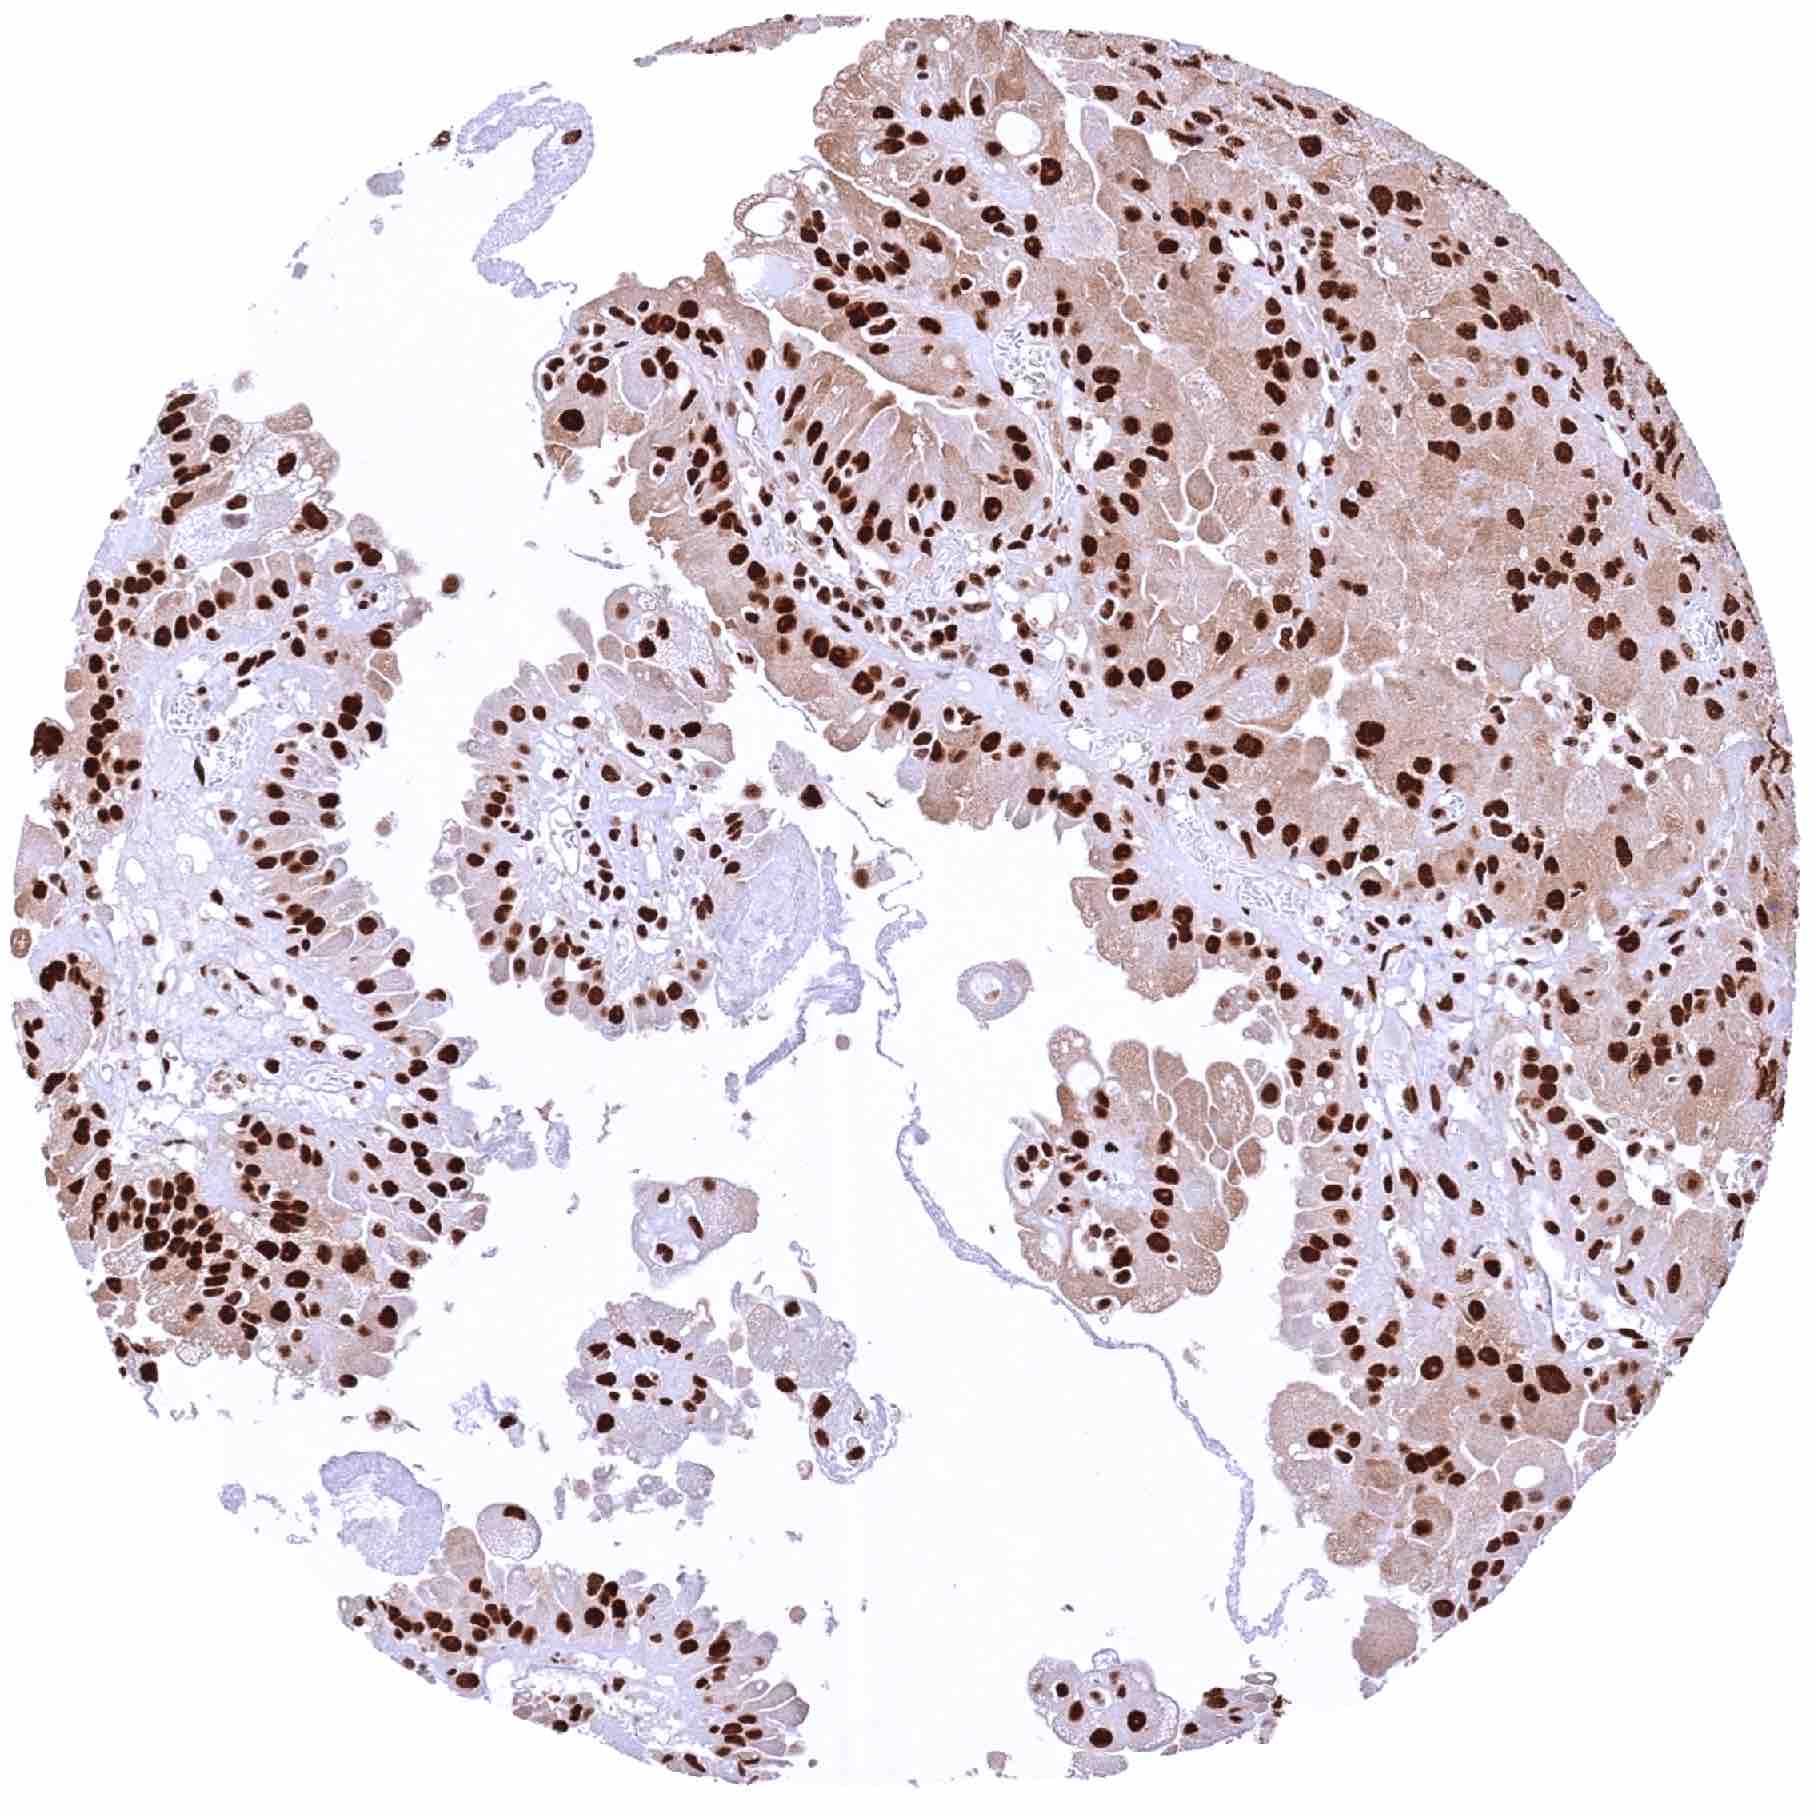

Kidney – Papillary renal cell carcinoma with strong GR staining of tumor cells